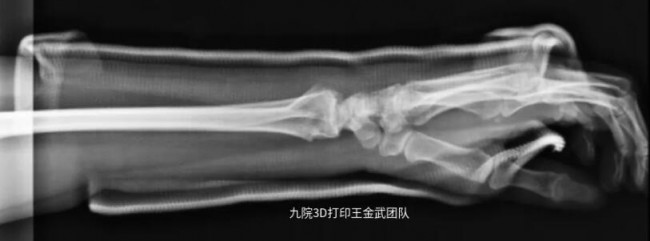

近日,上海第九人民医院王金武教授团队分享了通过3D打印外固定支具助力患者腕关节骨折恢复的案例。

患者左臂桡骨远端骨折,骨折固定后佩戴3D打印固定支具辅助恢复情况良好。